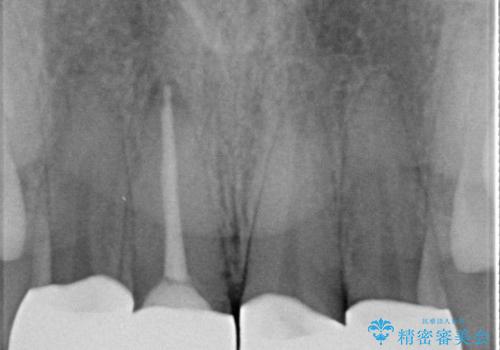

- 他院で治療した前歯の色が気になるということで来院された患者様です。前歯に色の差があり、レントゲンから内部にう蝕も見られたため、審美性に優れ、う蝕になりにくいオールセラミッククラウンで治療いたしました。